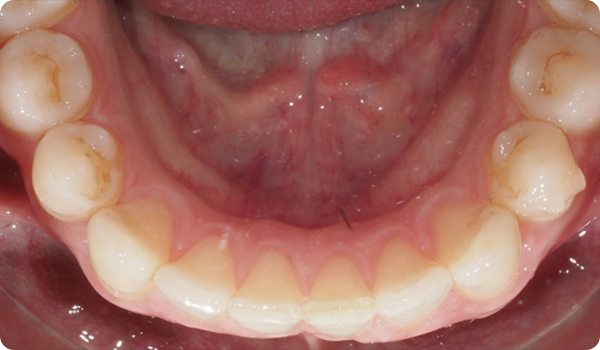

Kliniken skickar tre bilder och STL-filen från en skanning via Corus Link för att utvärdera fallet.

Leenden på plats

Med Right får dina patienter det leende de önskar, inom den tid de vill, på ett bekvämt och ”osynligt” sätt.

Att justera tänder med Right är den perfekta och mest konservativa grunden för framtida blekning eller facettbehandlingar som kommer att föra patientens leende till perfektion.